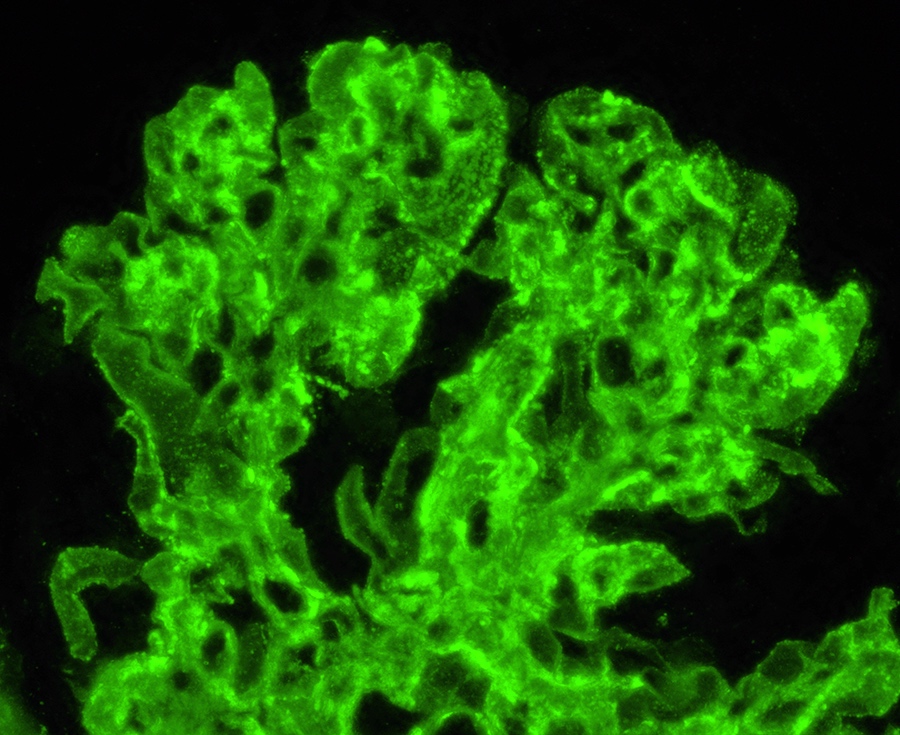

Immunofluorescence description

- Diagnostic criteria: IgG dominant full house immunofluorescence (positive IgG, IgA, IgM, C3, C1q, kappa and lambda light chains)

- Especially important are C1q positivity and extraglomerular immunostaining on the Bowman capsules, arteries, tubular basement membranes and in the interstitium

- Immunofluorescence staining is granular and may be subepithelial, intramembranous, subendothelial or mesangial

- In some cases, antinuclear antibody (ANA) test is seen with antibodies to IgG and the light chains

- Reference: Clin J Am Soc Nephrol 2019;14:1605

Immunofluorescence images

- Immunofluorescence microscopy: Up to 5 nonsclerosed glomeruli are available for evaluation. Mild to high intensity granular immunofluorescence staining was detected in the mesangial areas and less in the capillary walls with antibodies to IgG (4+), IgA (3+), IgM (2+), C3 (4+), C1q (3+), kappa light chains (4+) and lambda light chains (4+). Extraglomerular staining is seen on the arterial walls with antibodies to IgG.